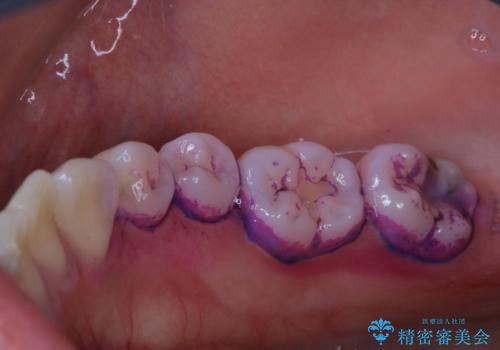

歯科衛生士によるクリーニング PMTC

- 半年ぶりの来院で、全体的なチェックとクリーニング希望でした。PMTC(自費クリーニング)60分コースを行いました。

PMTCとは、プロフェッショナル(歯科衛生士)メカニカル(機械的)トゥース(歯)クリーニング(清掃)の略です。歯科医院にて、いろいろな機械・材料を使用し汚れを落とします。

磨き残しや、細菌は歯の表面がザラザラしている部分につきやすいです。そのためPMTCを定期的に繰り返すことで、歯の表面がツルツルの状態である期間が長くなるため、虫歯や歯周病予防につながります。